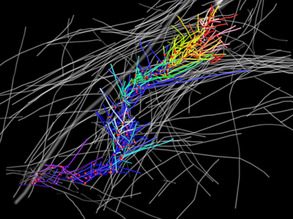

Tumour Trails